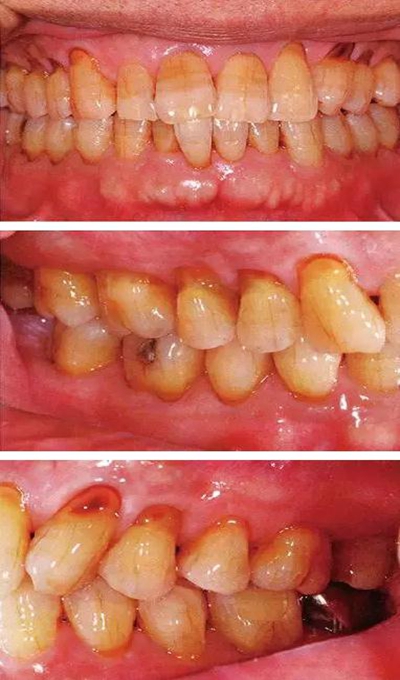

患有牙周病的牙周組織的臨床照片

56歲牙周炎男性的臨床照片

正在服用高血壓藥中的56歲男性。菌斑控制得不好。通過(guò)牙周探診,全頜有4~6mm的牙周袋,在X光片中可以看到全頜中度牙槽骨吸收,磨牙處一個(gè)地方是重度牙槽骨吸收。通過(guò)比較牙周病進(jìn)展?fàn)顟B(tài),邊緣部有大范圍浮腫(發(fā)紅、腫脹),和纖維性肥厚。這也可能是服用中的降壓藥的副作用導(dǎo)致的。因?yàn)檠例l、牙槽骨比較厚,牙齦呈架子狀。

55歲牙周炎男性的臨床照片

55歲男性抽煙患者(1天20支、抽煙35年)。菌斑控制得不好。通過(guò)牙周探診,全頜有4~9mm的牙周袋,有1~3度的根分叉部病變。通過(guò)X光片觀察,上頜前牙中度牙槽骨吸收,其他地方有中度牙槽骨吸收。受吸煙影響,牙齦纖維性肥厚,呈紅黑色。牙齦幾乎沒(méi)有浮腫和發(fā)紅,所以這個(gè)病例是從外觀上無(wú)法預(yù)測(cè)病癥嚴(yán)重程度的病例。

44歲牙周炎女性的臨床照片

44歲患有糖尿病病史(未治愈)。菌斑控制不良。通過(guò)牙周探診,全頜有4~8mm的牙周袋,在X光片中可以看到上頜前牙處中度牙槽骨吸收,磨牙處重度牙槽骨吸收。二次齲齒和根面齲齒也有發(fā)生。可以看到浮腫性腫脹,收到刺激后會(huì)出血。